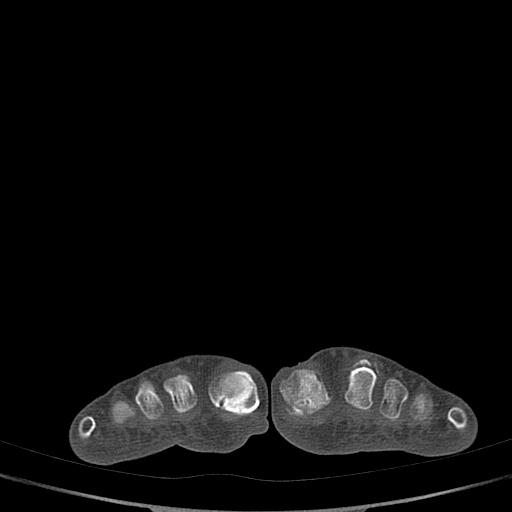

标题: CT13415:M72Y,跖趾关节病变,请会诊 [打印本页]

标题: CT13415:M72Y,跖趾关节病变,请会诊

男72岁左侧跖趾关节肿痛15年,查压痛。